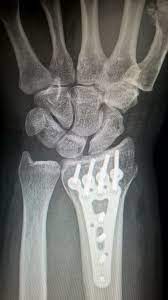

- X-레이 (X-ray): X-레이는 척추의 구조를 보는 데 사용됩니다. 디스크의 이상이나 척추 골절 등을 확인하는 데 도움을 줄 수 있지만, 디스크 자체의 세부 정보는 제공하지 않습니다.

- 컴퓨터 단층 촬영 (CT 스캔): CT 스캔은 X-레이와 유사하지만 목 부위의 구체적인 문제를 더 자세히 보여줄 수 있습니다. 특히 디스크 헤르니에이션과 같은 구조적인 문제를 확인하는 데 유용합니다.